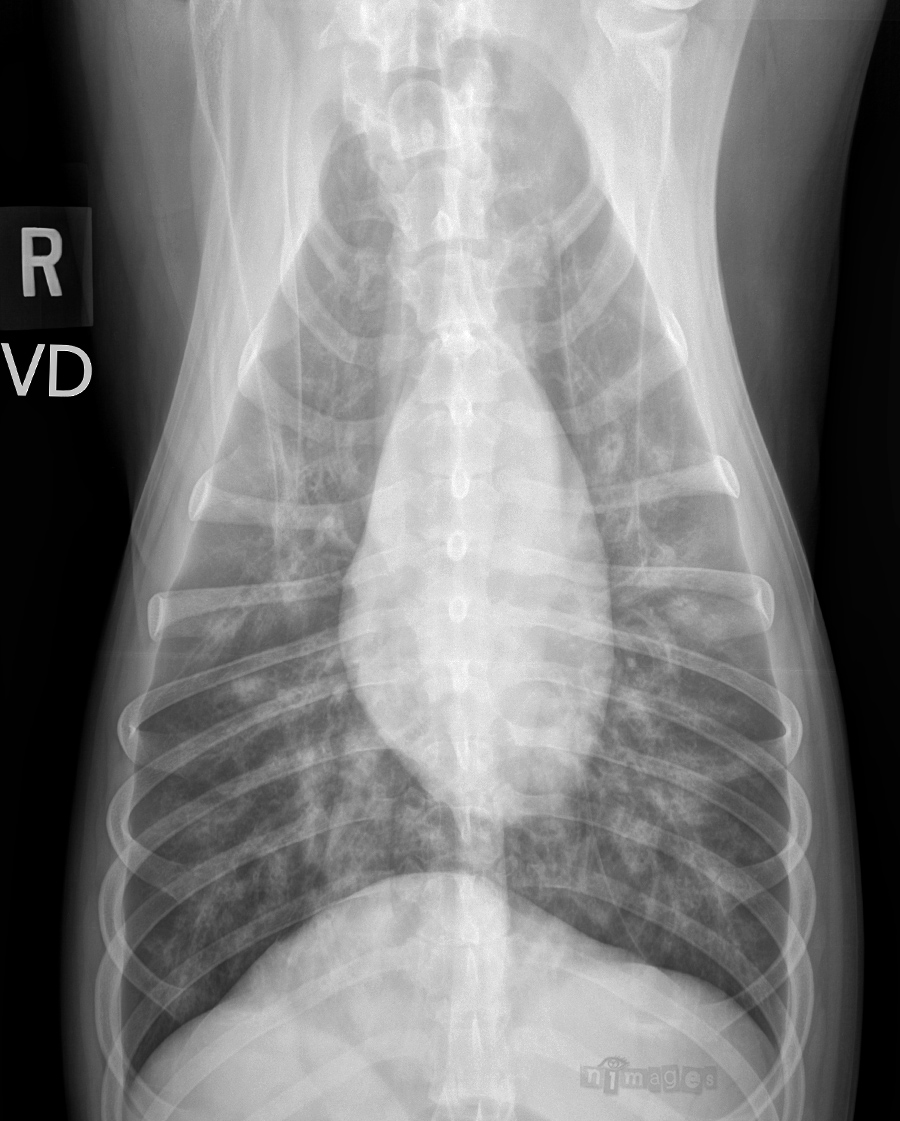

Ventrodorsale